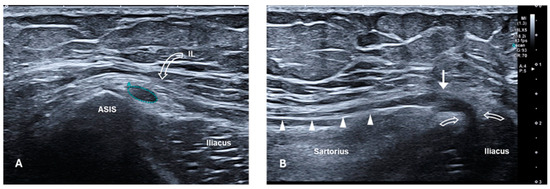

The diagnosis of MP was made based on clinical symptoms and signs: the Pelvic Compression Test and Tinel at the ASIS were positive in all the patients included in the study. In cases of suspected L2 radiculopathy, patients underwent electromyography and MRI of the lumbosacral spine to rule out causes related to the spine. Ultrasound of the LFCN was performed in some patients to confirm the presence of nerve compression and/or the presence of a neuroma or any other injury (Figure 1 and Figure 2).

Figure 1. High-resolution ultrasound of the LFCN with an 18 Mhz transducer in a patient with symptoms of meralgia paraesthetica. (A) Short-axis ultrasound at the level of the ASIS. The LFCN (outlined), located medial to the ASIS and deeper than the IL (curved arrow), appears hypoechoic and swollen with loss of the normal fascicular pattern (CSA = 8.8 mm2, normal range = 1–3 mm2). (B) Long-axis sonogram provides a panoramic view of the nerve course from the IL (curved arrows) to the proximal thigh, over the sartorius muscle. US confirms the neuromatous appearance of the nerve (white arrow), compressed at the level of the splitting of the IL (curved arrows). Distally to the neuroma, the nerve is normal (white arrowheads). ASIS, anterior superior iliac spine; IL, inguinal ligament; LFCN, lateral femoral cutaneous nerve; CSA, cross-sectional area; US, ultrasound.